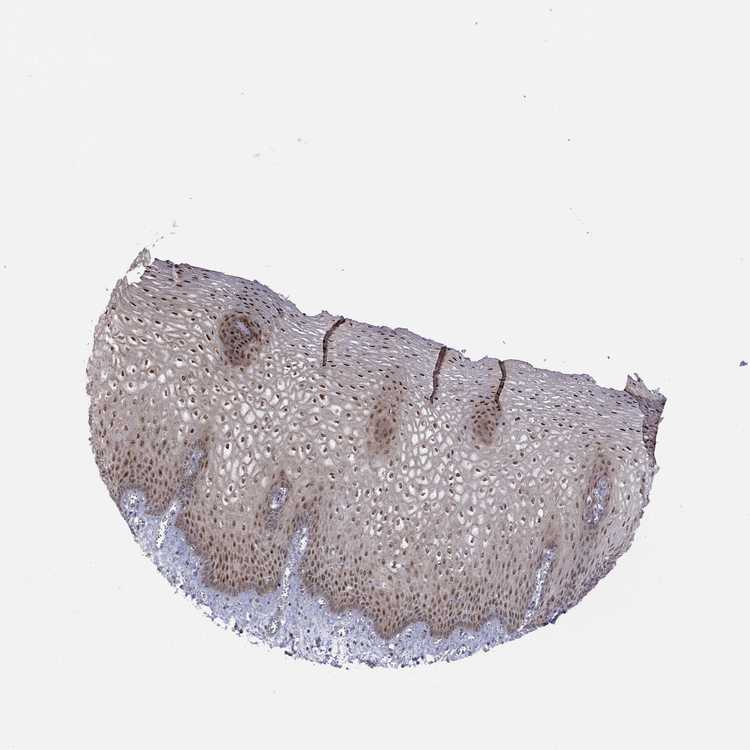

ESOPHAGUS - Antibody stainingi

Antibody staining in the annotated cell types in the current human tissue is reported as not detected, low, medium, or high, based on conventional immunohistochemistry profiling in selected tissues. This score is based on the combination of the staining intensity and fraction of stained cells.

Each image is clickable and will lead to virtual microscopy that enables deeper exploration of all samples and also displays staining intensity scores, fraction scores and subcellular localization as well as patient and tissue information for each sample.

Antibody HPA064006

Squamous epithelial cells High